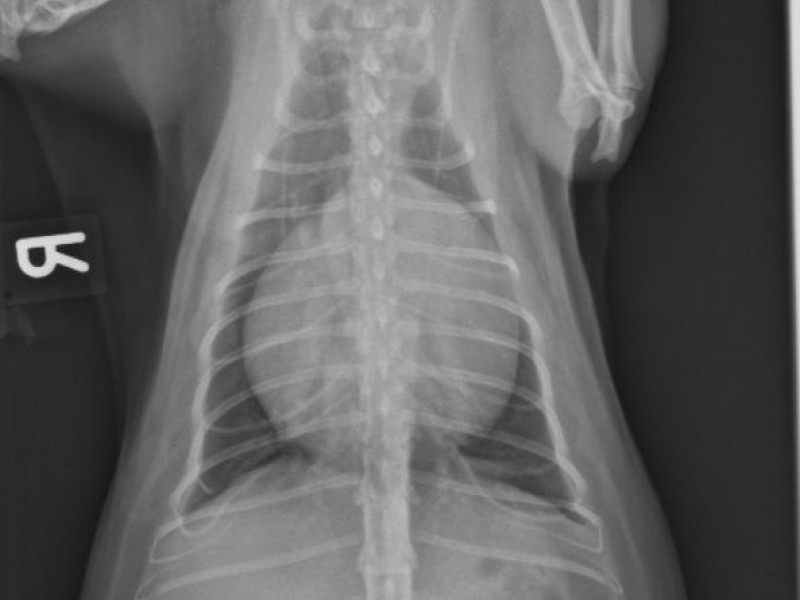

Féline-Thorax : A case of pericardial effusion in a cat

British shorthair, male 2 years

Tachypnea/dyspnea since 2 months, apathic

Pancytopenia

FIV/FelV positive

Clinical Exam:

Tachycardia 200 bpm, muffled heart sounds

Abdominal distention probably fluid

apathic

Pale muquous membranes

There is a severe globoid enlargement of the cardiac silhouette (more than 2,5 IC spaces), a mild distention of the caudal vena cava (wider than 1,5 times the aorta).

Normal appearing lungs, no congestion of the pulmonary vasculature.